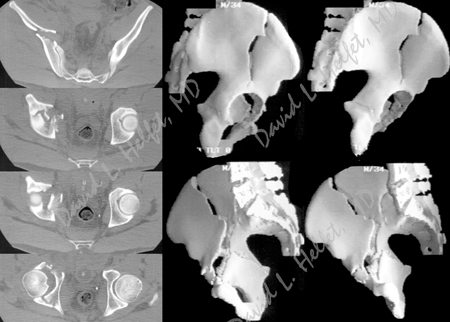

CT and 3D reconstruction images of the acetabulum further delineating the fracture pattern.